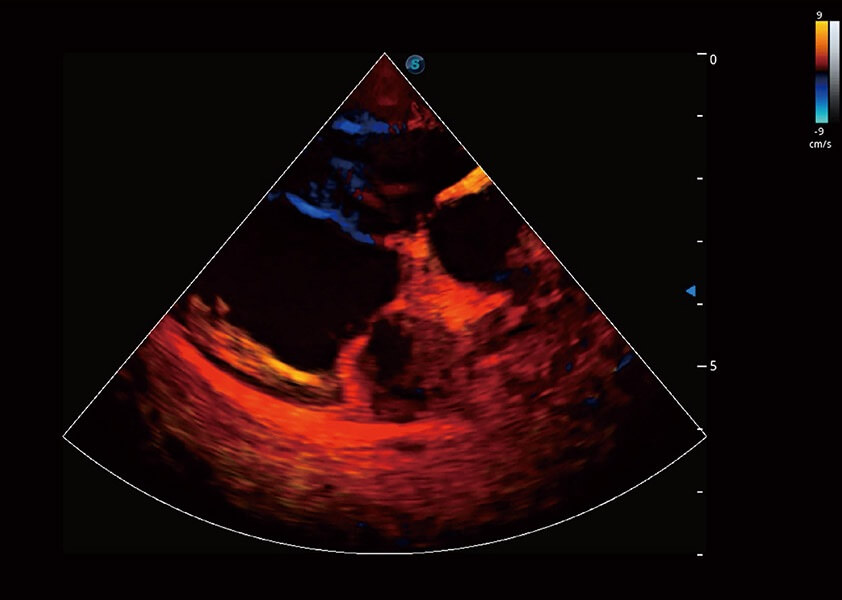

ProPet 60 作为一款高端台式动物超声设备,为动物医生的日常诊断提供了一系列贴合动物临床需求、解决临床实际问题的高级成像功能。凭借全系列高清探头,满足医生对腹部、心脏、生殖、浅表、肌骨等成像的所有需求,切实帮助您提升检查效率,提高诊断信心。

兽用彩色多普勒超声诊断系统

动物是人类最亲密的朋友和最值得信赖的伙伴。MILE米乐集团官网也一直致力于探索动物专用的超声影像解决方案。 全新推出的ProPet系列,是MILE米乐集团官网在动物超声影像智能化、专业化、精准化的一次跨越式革新。动物不能用言语来表述自己的不适,通过超声影像,ProPet系列搭建了动物医生与不同物种沟通的“桥梁”,为动物医生注入了“治愈之力”。